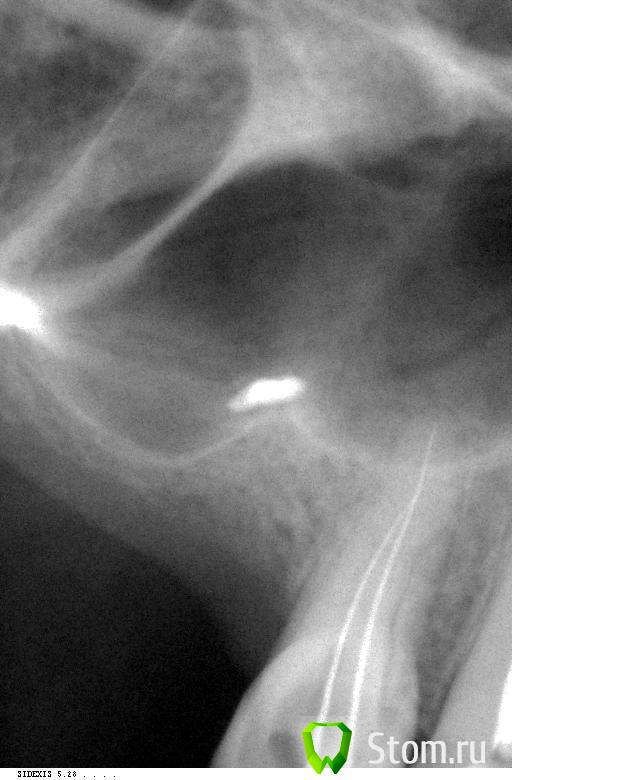

Catherine Опубликовано 5 марта, 2012 Автор Поделиться Опубликовано 5 марта, 2012 Собственно, вот снимки с иглами. Ссылка на комментарий

д-р Вит Опубликовано 5 марта, 2012 Поделиться Опубликовано 5 марта, 2012 хорошие снимки.дальше инструментами идти не стоит(имхо),помойте хлоркой разогретой с уз хорошенечко,при паковке получите картинку апекса. Ссылка на комментарий